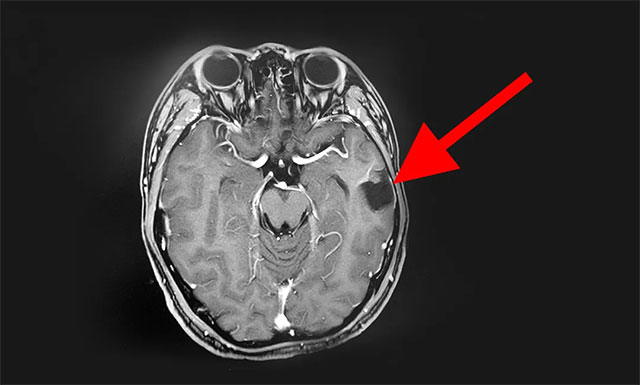

术后,患者病理标本检验结果为:海绵状血管瘤。经过一周多时间的康复治疗,患者恢复良好,其癫痫症状未再发作,家人总算放心了,再过几天后晨晨就可以出院了,但因晨晨体质较瘦弱,张先生想让儿子在医院多康复治疗一段时间再出院。

▲ 术后影像结果显示:患者海绵状血管瘤已切除